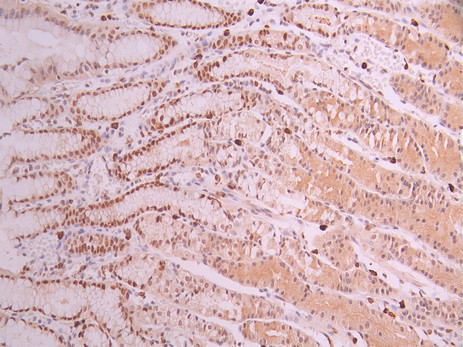

IHC image of CSB-RA207245A0HU diluted at 1:100 and staining in paraffin-embedded human gastric cancer performed on a Leica BondTM system. After dewaxing and hydration, antigen retrieval was mediated by high pressure in a citrate buffer (pH 6.0). Section was blocked with 10% normal goat serum 30min at RT. Then primary antibody (1% BSA) was incubated at 4°C overnight. The primary is detected by a Goat anti-rabbit polymer IgG labeled by HRP and visualized using 0.05% DAB.